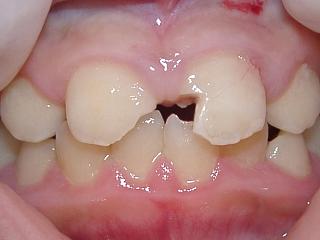

複雑性歯冠破折:露髄を伴い、エナメル質、象牙質、セメント質に及ぶ破折 (図2、3)

複雑性歯冠破折の場合(図2,3)

強い冷温水痛、あるいは、強い自発痛があります。

歯髄保護をしたのち、レジン樹脂などで破折部の修復を行います。

しかし歯髄への傷害が大きい場合には歯髄除去(抜髄)が必要に成ります。